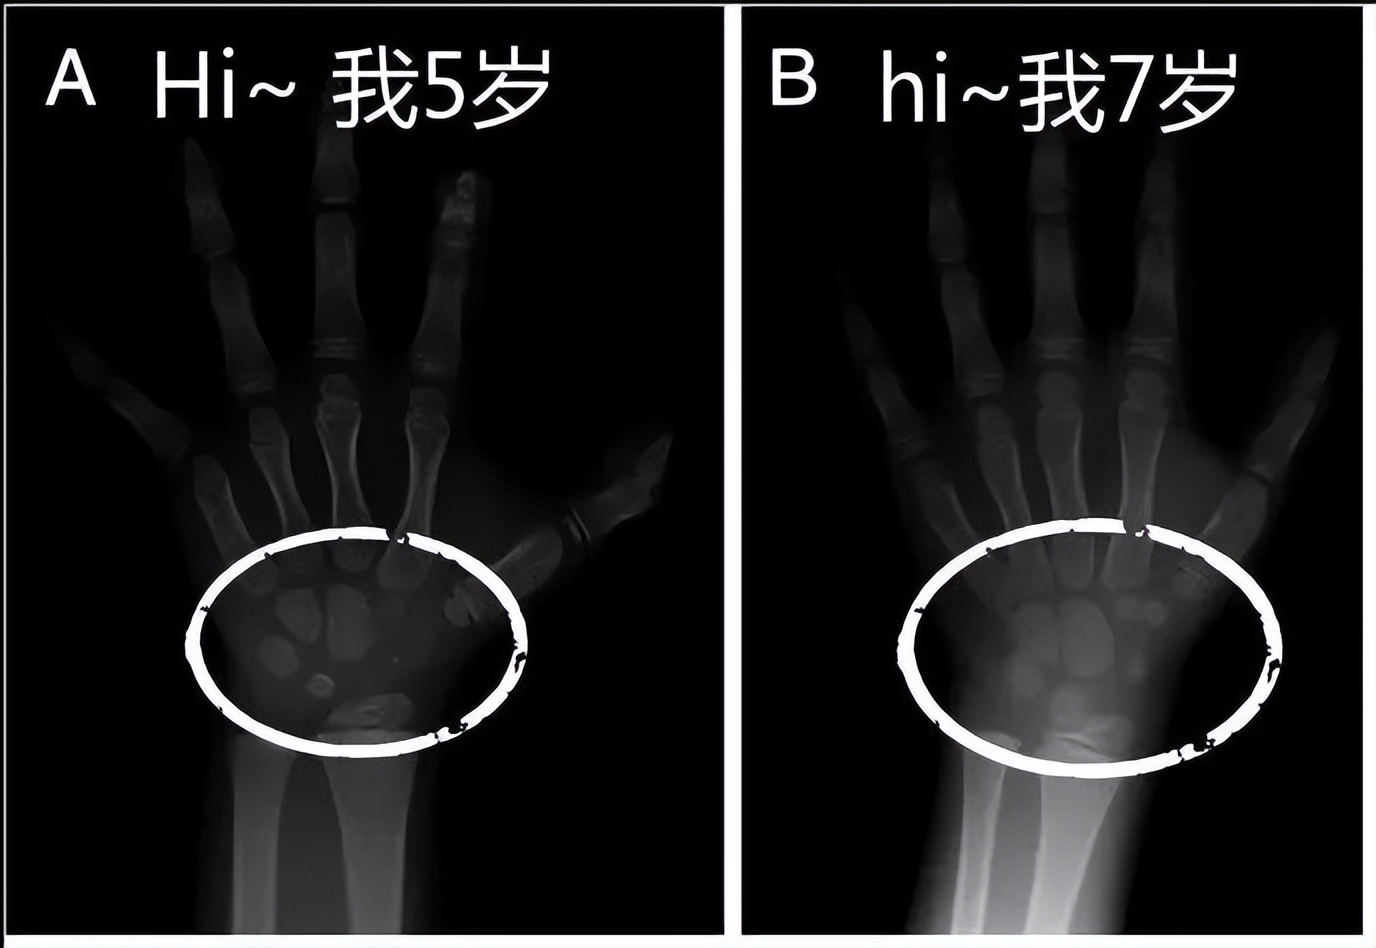

骨龄能有效反映人体的成熟程度,对成人身高和青春期发育都有重要影响,因此,骨龄评价在临床医学中应用广泛,是影响儿童生长发育疾病诊断、鉴别诊断和疗效观察的重要辅助手段。

首先要知道的是,骨龄是反映其年龄和发育的非常重要的参考数据,如果孩子的骨龄太大,说明孩子的生长发育太快,会导致后面不长。